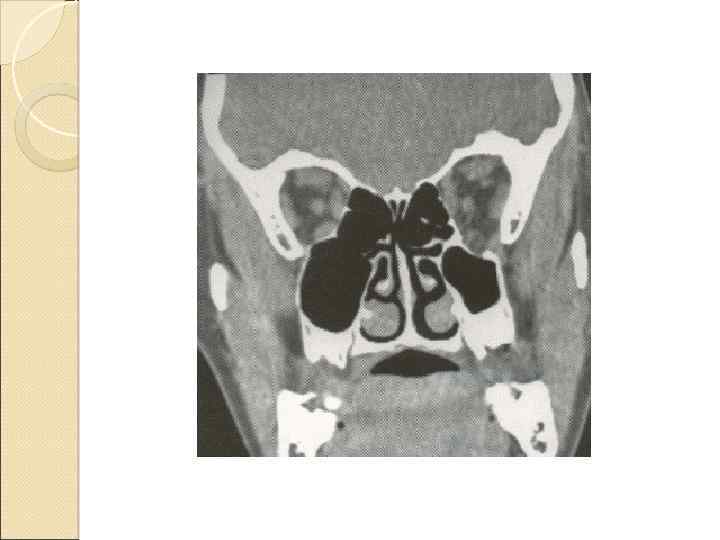

а – с повреждением верхнечелюстной пазухи и внедрением в нее костных отломков; б – без повреждена пазухи.